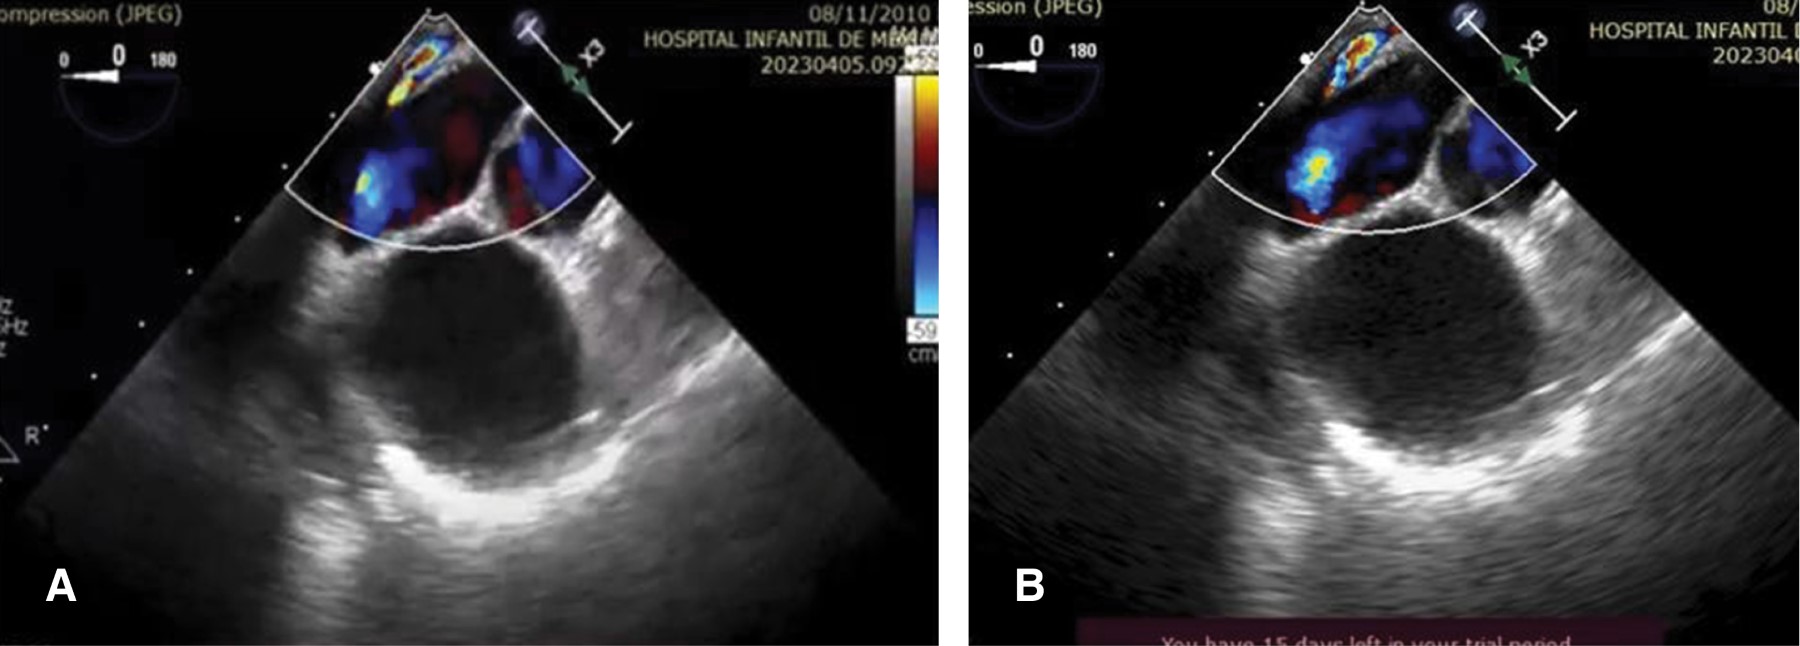

A 12-year-old female with a history of non-obstructed TAPVC to the coronary sinus underwent total correction at nine months of age. At one year of age, an echocardiogram with color flow Doppler (Figures 1 and 2) documented obstruction of the right PV with a mean gradient of 13 mmHg. Subsequently, a contrast-enhanced computed tomography angiography (angioTAC) was requested (Figure 3), which reported drainage of PV with patent flow. No collector was identified, but three PV were observed, two on the left and one on the right. In the lower left and right PV, a small hypodense band was noted, a finding suggestive of a partial septum at each origin. Reported diameters were as follows: superior right PV of 3.4 mm, superior left PV of 3.2 mm, and inferior left PV of 3.4 mm. The patient showed appropriate evolution and was lost to follow-up.

Figure 1

Figure 2